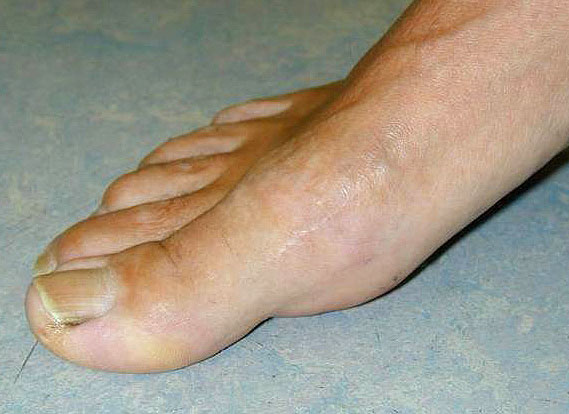

Entwickelt sich nach Hallux valgus Korrektur eine Hallux varus Fehlstellung, orientiert sich das weitere Vorgehen vor allem am Zustand des Großzehengrundgelenks. Liegen bereits erhebliche degenerative Veränderungen vor, so ist die Arthrodese das zuverlässigste Verfahren die Stellung dauerhaft zu korrigieren und die Schmerzen zu beseitigen.  Wird eine Hallux varus Fehlstellung frühzeitig erkannt und revidiert, ist häufig ein Gelenkerhalt möglich.

1) Arthrodese Großzehengrundgelenk

Schlüssel für eine erfolgreiche Arthrodese am Großzehengrundgelenk ist die exakte Stellung der Zehe. Eine freie Beweglichkeit im Interphalangealgelenk sollte vorhanden sein, die Grundphalanx sollte den Abrollvorgang nicht behindern und gleichzeitig dorsal nicht im Schuh scheuern. Es ist anzustreben, dass bei Flexion im Interphalangealgelenk die Großzehenbeere den Boden erreicht.